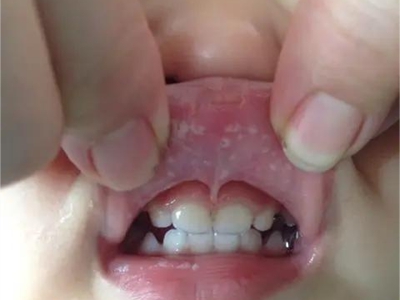

唇内侧

白点

鹅口疮下唇内侧白色小点图

鹅口疮好发于小儿,表现为下唇内侧黏膜出现乳白色的小点,周围无炎症反应,擦掉白色小点容易弄伤黏膜,甚至出血,因此建议不要强行擦除。